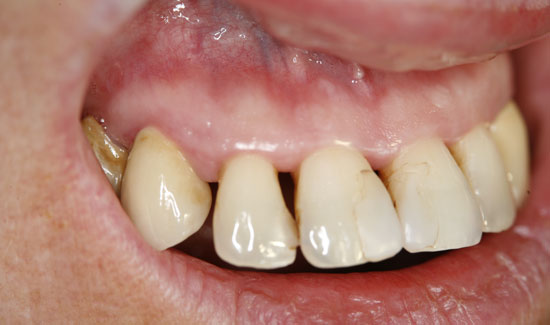

Abb. 3: Zustand nach Ozontherapie. Chlorhexidinverfärbung der Zähne